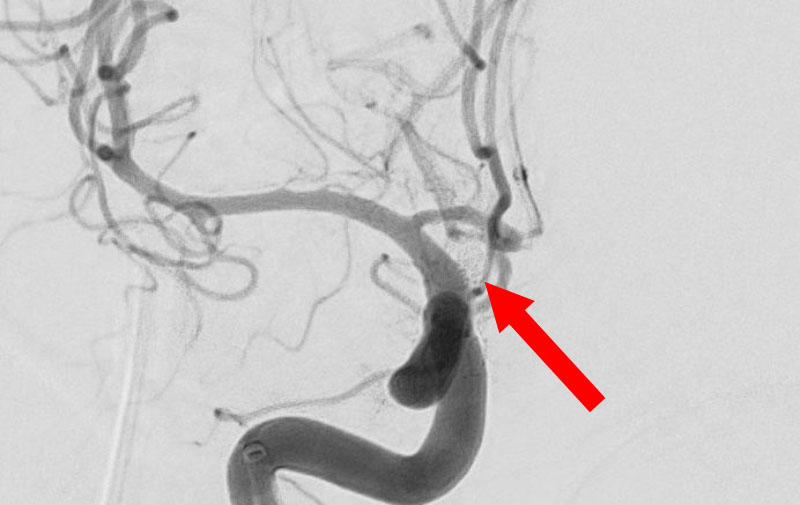

'25年11月

くも膜下出血

右内頚動脈後交通動脈

分岐部動脈瘤破裂

60代

救急外来

No.1593 手術前

No.1593 手術中

No.1593 手術後